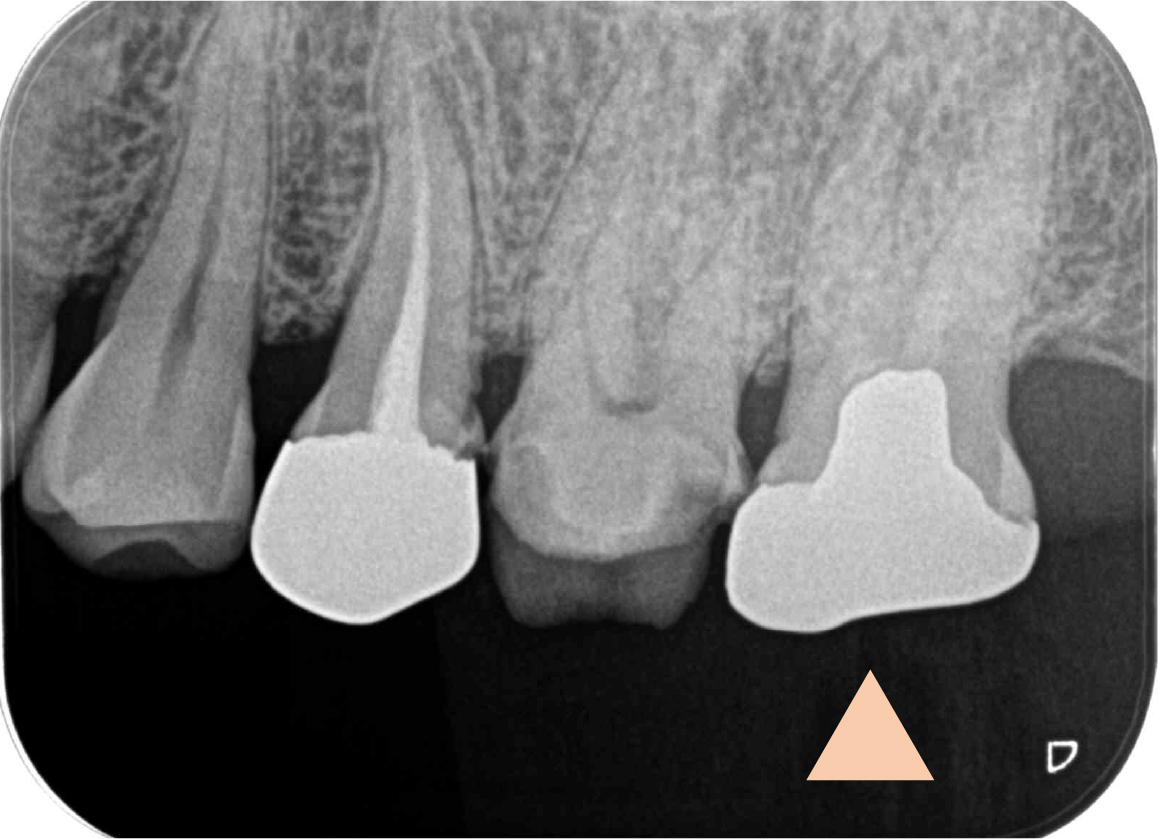

左上6番(第一大臼歯)のインレーが脱離しており、内部でう蝕が大きく進んでいる状態でした。長期にわたりう蝕が隠れていたことにより、根管は石灰化しておりやや狭窄していることが疑われました。隠れた根管が存在している可能性(MB2根)もあり、丁寧かつ慎重に治療を進める必要がある状態でした。

根管充填直後の写真です。緊密に封鎖が得られていることを確認し、治療は完了です。治療当時は土台を立てる際にスクリューポストという材料を使用していましたが、現在はファイバー製のポストを使用しています。

レントゲン的にも根の先の状態は良好であり、修復物の適合もしっかり合っていることがわかります。